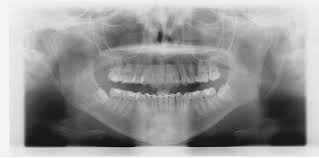

Häufig verläuft ein Nerv entweder durch die Wurzeln oder am Zahn entlang. Und bei nicht wenigen war es der fall dass der eingriff nah am nerv vorgenommen wurde das risiko also da war. Bevor ich meinen körper über jahre mit schmerzmitteln schädige und schmerzen leide würde ich mich diesem eingriff unterziehen.

Sie liegen sehr nah am Nerv weshalb der Arzt nur zwei auf Einmal zieht. Bei der lokalen Narkose besteht das Risiko vor allem dadurch dass durch die Nadel ein Nerv beschädigt wird.